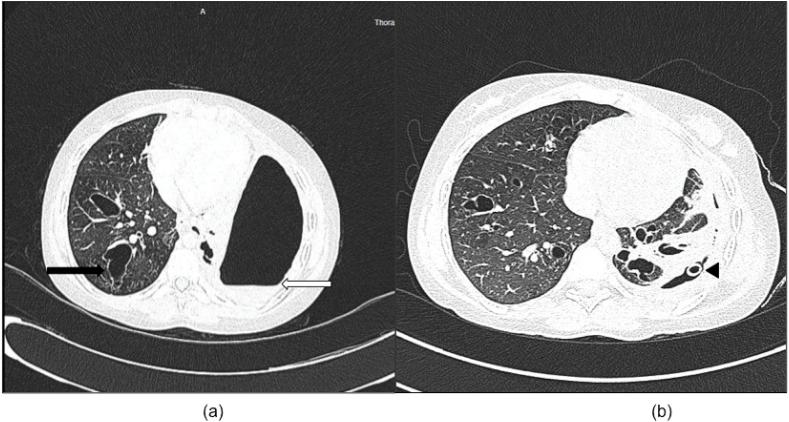

A unique case of hydropneumothorax in allergic bronchopulmonary aspergillosis.

Allergic bronchopulmonary aspergillosis (ABPA) is an immunologically mediated disease characterized by a hypersensitivity reaction to fungal colonization by Aspergillus. Hydropneumothoraces and bronchopleural fistulae are rare occurrences in patients with ABPA. However, the diagnosis of ABPA is important to consider, as it is easily treatable with specific therapy. We report an unusual case of a patient with ABPA who presented to us with hydropneumothorax with bronchopleural fistula.